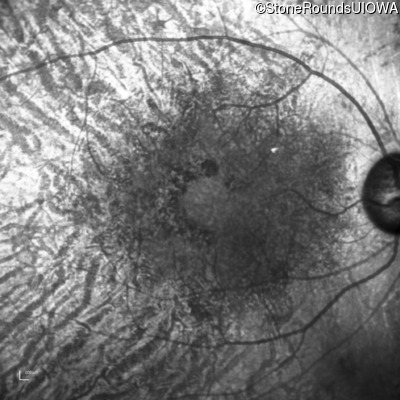

Age at visit: 62 years

OD OS

This 62 year old man had poor night vision as a teenager and developed difficulty with his peripheral vision in his early forties. His parents both grew up in the small village in Taiwan.

Diagnosis & molecular findings

AR Retinitis Pigmentosa EYS Cys2139Tyr TGT>TAT Cys2139Tyr TGT>TAT AR